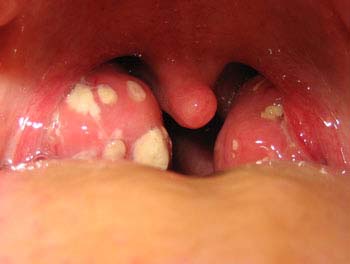

Tonsils play a vital role in protecting the body against harmful bacteria and viruses. However, when the immunity reduces, the tonsils fall prey to these infective organisms thereby resulting in swelling (inflammation) of the tonsils

Tonsillitis is much more than just a simple sore throat. It can be a source of danger for growing kids.